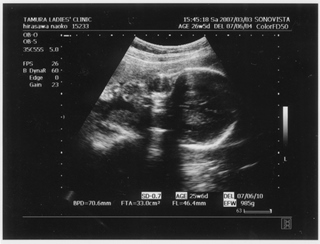

× [PR]上記の広告は3ヶ月以上新規記事投稿のないブログに表示されています。新しい記事を書く事で広告が消えます。 9ヶ月(32週と5日) 体重:2072g BPD(頭を上から見た耳から耳の幅のような感じ):84.6㎜ FTA(お腹の断面):60.8平方㎝ FL(大腿骨長 太ももの骨の長さ):61.2㎜ 9ヶ月(35週と2日) 体重:2583g BPD(頭を上から見た耳から耳の幅のような感じ):90.2㎜ FTA(お腹の断面):72.8平方㎝ FL(大腿骨長 太ももの骨の長さ):64.8㎜ 久しぶりの記事アップです ![]() なんだかあっという間にGW終わってしましましたね~ ![]() きのうは雨のせいでだらけてしまって、記事書く予定ができませんでした ![]() ダンナっちには『雨降って ナオコ 動かず』といわれています・・・ ![]() さてさて、5月2日(35週と2日)の内診では、 子宮口が1センチ開いてきてることが発覚 先生に「もう少し入れておいてよ 張ったら休まなきゃダメ」と言われ、 薬 まで出されました。子宮の筋緊張状態をやわらげて、早産を防止 するんだそうです。 「慣れるまでは心臓がドキドキしたり、 手が震えたりしますけど、大丈夫ですから」 と先生から説明を受けて、家で飲んでみると、 ほんとにドキドキ して、手もピクピク してきて、なんかラリった妊婦状態で不思議でした。 今週に入って、だいぶ慣れたようでそんなにラリっては いないけど、飲んでから1時間くらいは運転を控えています ![]() ベイビー自体は2500gをすでに超えて、動きも活発で元気にしています ![]() 1センチ開いてもなかなか進まないこともあるし、どうなるかはわかりません ![]() でも、ベイビーがお腹から出てきて自分で呼吸をするために、 必要な肺のサーファクタント(界面活性物質)の分泌は、妊娠33~36週ころから になります。 哺乳反射といって、ベイビーがおっぱいを飲むための反射的に吸い付く能力は 32~34週で完成するそうです。 網膜の血管が完成するのは35週前後だそうです。 つまり、わたしは今週臨月(36週)に入りましたが、 やっぱり正期産である37週からの出産が望ましいみたいです ![]() ![]() 医療も発達してきてるし、 ほぼ完成しているので生きられないことはぜんぜん無いんですけど、 十分に成長して「時」が満ちて生まれるのが一番みたいですね~ ![]() 「はやく会いたいけど、あと3週間くらいお腹の中にいてね~」 とベイビーに言っています ![]() 薬をもらってから、「張り」を意識するようになったんですけど、 けっこう張るんですよね~ 張るとなんとも動きづらい ![]() パンパンで重みのある厚手のゴムボール を持って歩くような・・・そして、 膀胱圧迫![]() ![]() ![]() トイレ行くにも駆け込む動作がつらい 歩けない![]() 、走れない![]() ![]() 悲惨な結末 ![]() ![]() ![]() ![]() を迎えまいとして、キュッと閉める運動をせざるをえなくなります・・・ ![]() PR